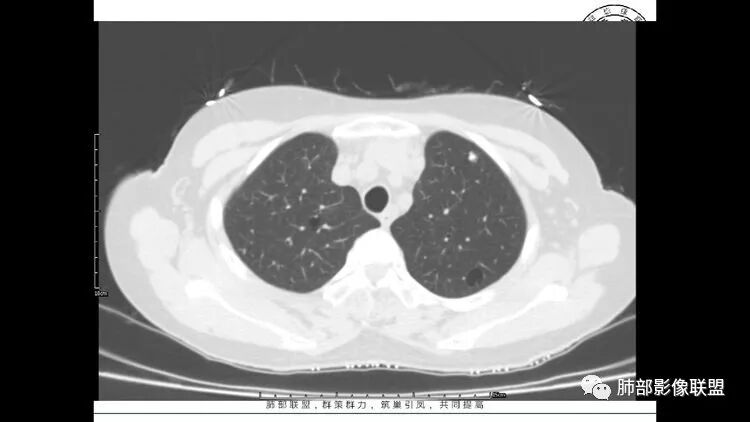

左肺下叶混杂密度病灶,其内可见空泡,周围ggo清楚,考虑浸润性腺癌。双肺散在多发薄壁囊腔和实性结节,以胸膜下及血管旁分布位于,气囊可见血管贴边征,双肺小叶间隔及中央间质增厚,局部可见磨玻璃影及树芽征,纵隔内淋巴结肿大,考虑LIP

综上,考虑左下肺浸润性腺癌+LIP

双肺多发大小不等囊腔,可见薄壁,部分囊腔内可见血管影,伴双肺多发结节,结合患者眼病及类风湿病史,考虑LIP可能大。另左肺下叶磨玻璃结节,边界清晰,内可见空泡,伴纵膈多发肿大淋巴结,不除外浸润性腺癌可能。

双肺多发囊腔伴结节 部分结节周围有晕 边缘清 前纵隔多发淋巴结增大 考虑lip伴淋巴瘤?